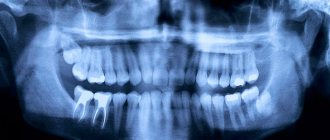

• X-ray positivity, thanks to which full control over the quality of the filling is possible;

The better the paste is condensed, the better the radiopacity of the material on the radiograph. It is enough to fill the canal up to the top, and in poorly passable canals the entire passable part, with a developed growth zone, 1-2 mm short of reaching the top of the canal. When removing the material beyond the root tip, no problems arise due to the high alkalinity and complete immunoindifference of the material. Next, the cavity is closed with cement.